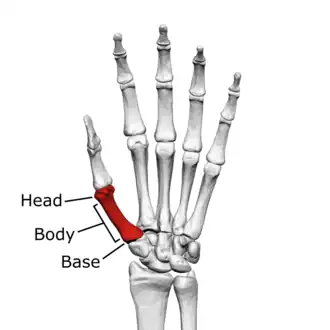

The first metacarpal bone or the metacarpal bone of the thumb is the first bone proximal to the thumb. It is connected to the trapezium of the carpus at the first carpometacarpal joint and to the proximal thumb phalanx at the first metacarpophalangeal joint.

The first metacarpal bone is short and thick with a shaft thicker and broader than those of the other metacarpal bones. Its narrow shaft connects its widened base and rounded head; the former consisting of a thick cortical bone surrounding the open medullary canal; the latter two consisting of cancellous bone surrounded by a thin cortical shell. [1]

Head

The head is less rounded and less spherical than those of the other metacarpals, making it better suited for a hinge-like articulation.

Body/Shaft

The body or shaft is thick and broad — averaging 6 to 11 millimetres (0.24 to 0.43 in). On its dorsal side, the shaft is flat and wide, while the anteroposterior side is less pronounced; usually resulting in an oval-triangular cross-section.

Base

The base is significantly different from the bases of the other metacarpals. It is trumpet-shaped and ends in a saddle-shaped articular surface matching that of the trapezial articular surface. The configuration of the thumb carpometacarpal joint plays an important role in the mechanism of opposition. The articular surface is delimited by a thick, crest-like ridge extending around its circumference.